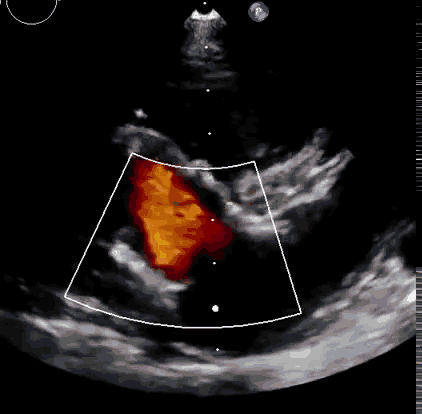

上海中山醫(yī)院葛均波院士、錢菊英院長(zhǎng)、周達(dá)新教授、潘文志教授、潘翠珍教授、李偉教授共同完成此次臨床前研究。術(shù)后葛均波院士對(duì)Lux-Valve Plus的器械操作性能給予了高度評(píng)價(jià),DSA和超聲影像也顯示出在本次研究中Lux-Valve Plus的安全性和有效性俱佳。

Lux-Valve是全球第一款具有我國(guó)完全自主知識(shí)產(chǎn)權(quán)的經(jīng)導(dǎo)管介入三尖瓣置換系統(tǒng),利用前瓣夾持及室間隔錨定的復(fù)合方式進(jìn)行瓣膜裝置的固定,不依賴瓣環(huán)徑向支撐力,同時(shí)采用自適應(yīng)復(fù)合裙邊材料,有效的貼合密封柔軟的三尖瓣瓣環(huán),針對(duì)于三尖瓣返流的患者有優(yōu)異的療效。Lux-Valve Plus采用全新的經(jīng)血管輸送系統(tǒng),經(jīng)頸靜脈入路創(chuàng)傷更小,可以進(jìn)一步降低手術(shù)風(fēng)險(xiǎn)。相信在后期正式臨床研究開展中,Lux-Valve Plus必定會(huì)為更多的三尖瓣反流患者帶來(lái)福音。